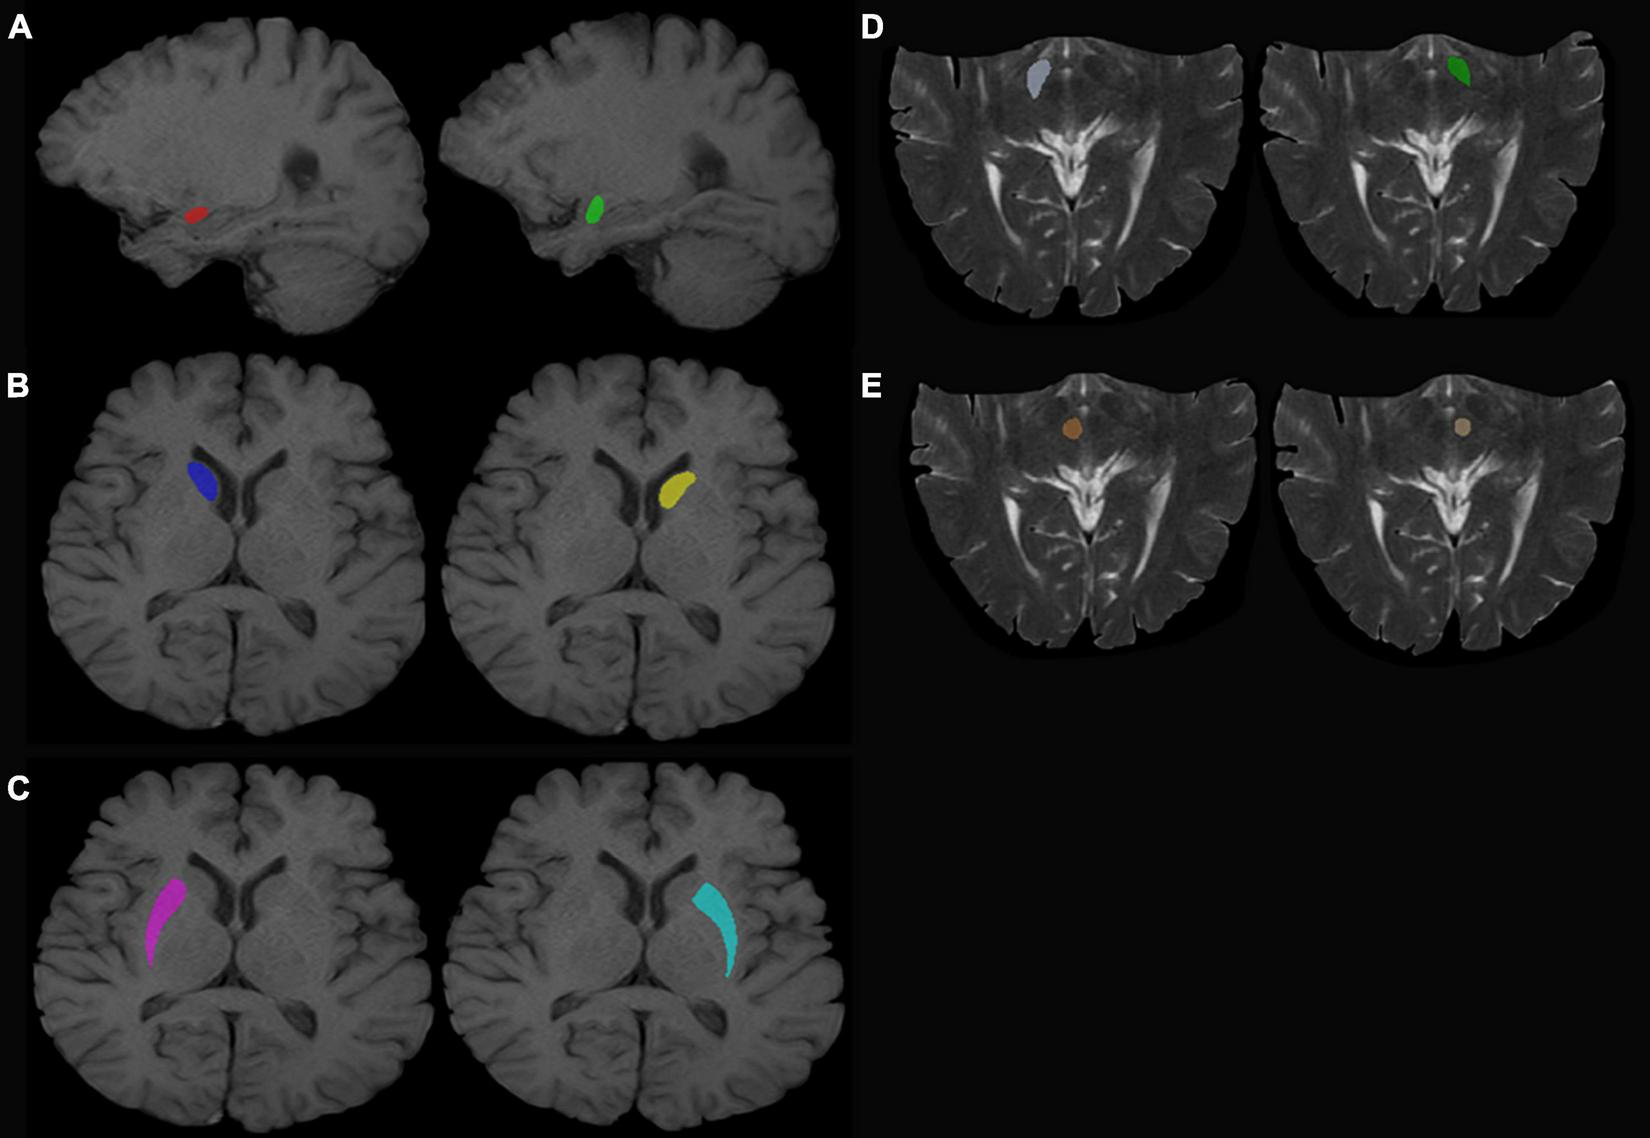

T1-weighted (T1W) images and T2-weighted (T2W) images were manually labeled using ITK-SNAP (Huang et al., 2016; Wilson et al., 2019)1 by three experienced radiologists. The labeled ROI in the T1W image included the bilateral amygdala, bilateral caudate nucleus head, and bilateral putamen. The labeled ROI in T2W images included the bilateral substantia nigra and red nucleus (Figure 1, for example, images).

FIGURE 1

Regions of interest. (A) Left (green) and right (red) amygdala. (B) Left (yellow) and right (dark blue) caudate nucleus head. (C) Left (sky blue) and right (purple) putamen. (D) Left (dark green) and right (white) SN. (E) Left (beige) and right (red) red nucleus.